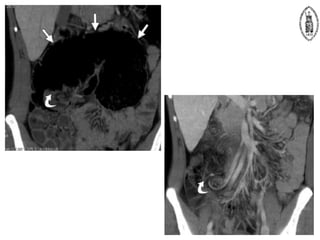

Acute appendicitis

 CT

– Appearance on CT

• Filling of appendix with oral contrast is an important negative feature

• Normal appendix wall 1-2mm in thickness

• Periappendiceal fat should appear homogenous

– CT diagnosis of acute appendicitis can be made if

• Abnormal appendix identified

– Appendix diameter > 6mm

– With homogenously enhancing wall

– Mural edema may produce a target sign

– Periappendiceal inflammation in 98%

» Fat stranding

• Calcified appendicolith with pericecal inflammation

– Perforated appendicitis

• Accompanied by pericecal phlegmon or abscess

• Associated findings

– Extraluminal air

– Ileocecal thickening

– Localized lymphadenopathy

– Peritoneal enhancement

– Small bowel obstruction

Inflamed appendix with a target

sign : enhancing serosa and mucosa

seperated by oedematous fluid in wall

Appendix abscess : Ring enhancing

collection with adjacent appendicolith

Appendicitis : dilated appendix

; appendicoliths ; adjacent fat

stranding